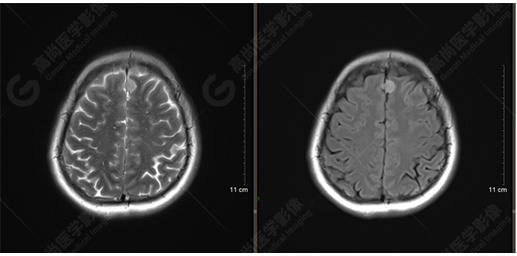

下面是其他神經(jīng)纖維束成像:

胼胝體束、雙側(cè)扣帶束及額枕束形態(tài)可,纖維束未見明顯破壞,未見明顯稀疏減少。大腦鐮旁的病灶對神經(jīng)纖維束走行并沒有什么影響。